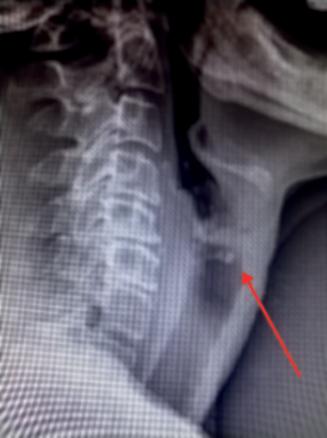

La radio standard, prescrite en urgence, met en évidence un corps étranger (CE) situé au niveau du carrefour aéro-digestif (fig. 1). Une ablation par laryngoscopie est préconisée.

Le bilan radiologique comporte des clichés cervicaux, thoraciques et éventuellement un abdomen sans préparation. En cas de CE radio-opaque (objet métallique, pièce de monnaie...), il permet de déterminer sa taille, sa nature et sa localisation, de dépister d’éventuelles complications et de surveiller sa progression dans le tube digestif. Il n’est pas systématique en cas d’incarcérations d’aliments dans la muqueuse digestive.